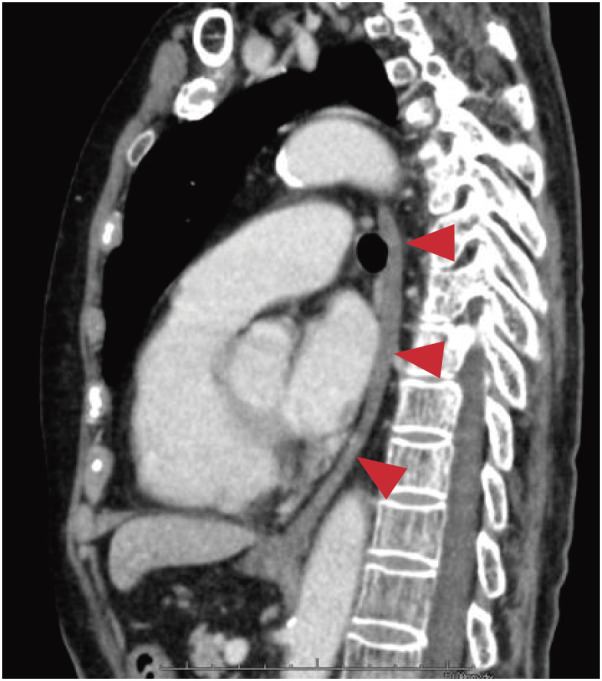

Case presentation: The patient was a 72-year-old woman. At 20 years of age, she ingested an alkali substance in a suicide attempt, leading to the development of corrosive esophagitis. Surgery was initially considered for esophageal atresia but was deemed unfeasible at the time; therefore, gastrostomy was performed instead. Subsequently, for over 50 years, she manually chewed food and inserted it into her gastric tube. She was urgently transported to a nearby hospital after her general condition deteriorated due to an influenza infection. During hospitalization, her nutritional intake was reassessed, and given her strong desire for oral intake, she was referred to our hospital for surgical treatment. Her gastric mucosa was intact, and imaging revealed mild mediastinal inflammation and fibrosis, rendering esophageal resection and reconstruction feasible. Considering surgical invasiveness, we opted for a mediastinoscopic esophagectomy and performed posterior mediastinal reconstruction using a gastric tube with a cervical hand-sewn anastomosis. The patient recovered without any complications and was discharged. Although postoperative aspiration and swallowing disorders were anticipated, the patient experienced none, likely because her unique self-feeding method preserved the functions of her masticatory and swallowing muscles.